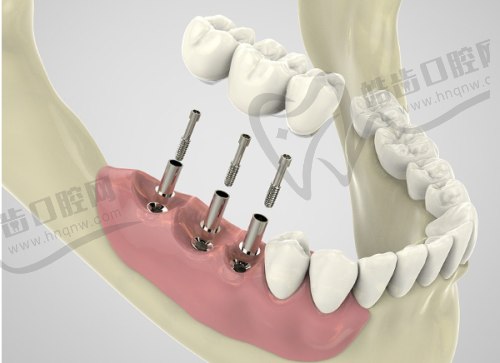

適合人群:缺牙想「即刻有牙食飯」嘅長者、牙骨量不足嘅煙民(鼎植有「即刻種即刻用」技術)。

「斜向種植術」:針對牙骨薄嘅人,種植體斜住入去,唔使植骨,手術時間縮短到30分鐘,「我老公食煙多年牙骨差,香港醫生話要植骨等3個月,鼎植醫生用斜向種植,當日種完當日食粥,一個月後食到燒鵝!」(住天水圍嘅陳太)。

終身保養:種植體提供終身保養,每年免費洗牙檢查,「香港種牙後續保養每次收1000HKD,呢度免費,長遠計更抵!」

價錢參考:瑞士ITI種植體13800人民幣(約15000HKD)/粒,比香港平1.3萬HKD。